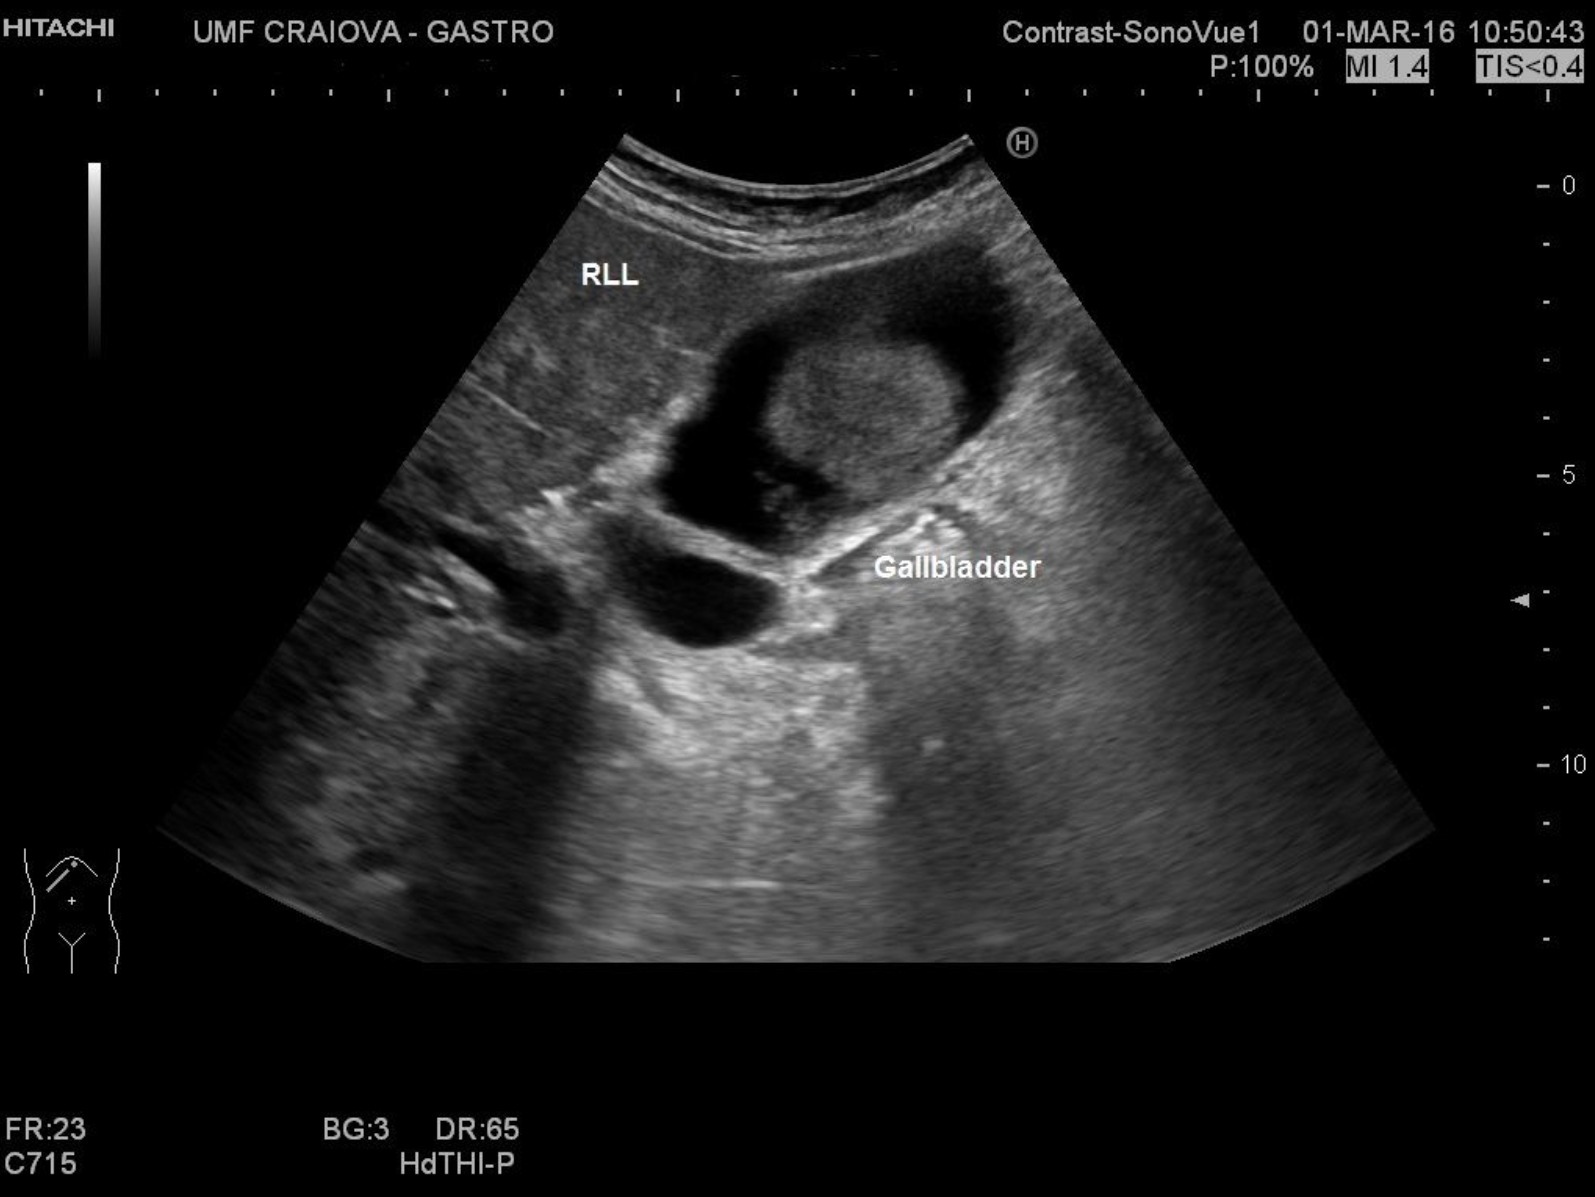

Sludge in gallbladder [1 image] Categories BASIC ULTRASOUND IMAGESGallbladder and Bile DuctsGallstones and Sludge in Gallbladder TITLE: Sludge in gallbladder DESCRIPTION: 62 year female with Hepatitis B virus-related cirrhosis with aggregated sludge and an incomplete septum EMAIL CONTACT:constantinescu.codruta@yahoo.com KEYWORDS:gallbladder, gallbladder ultrasound, aggregated sludge, incomplete septum Related postsJanuary 5, 2021Walled-off pancreatic necrosis [2 images]Read more